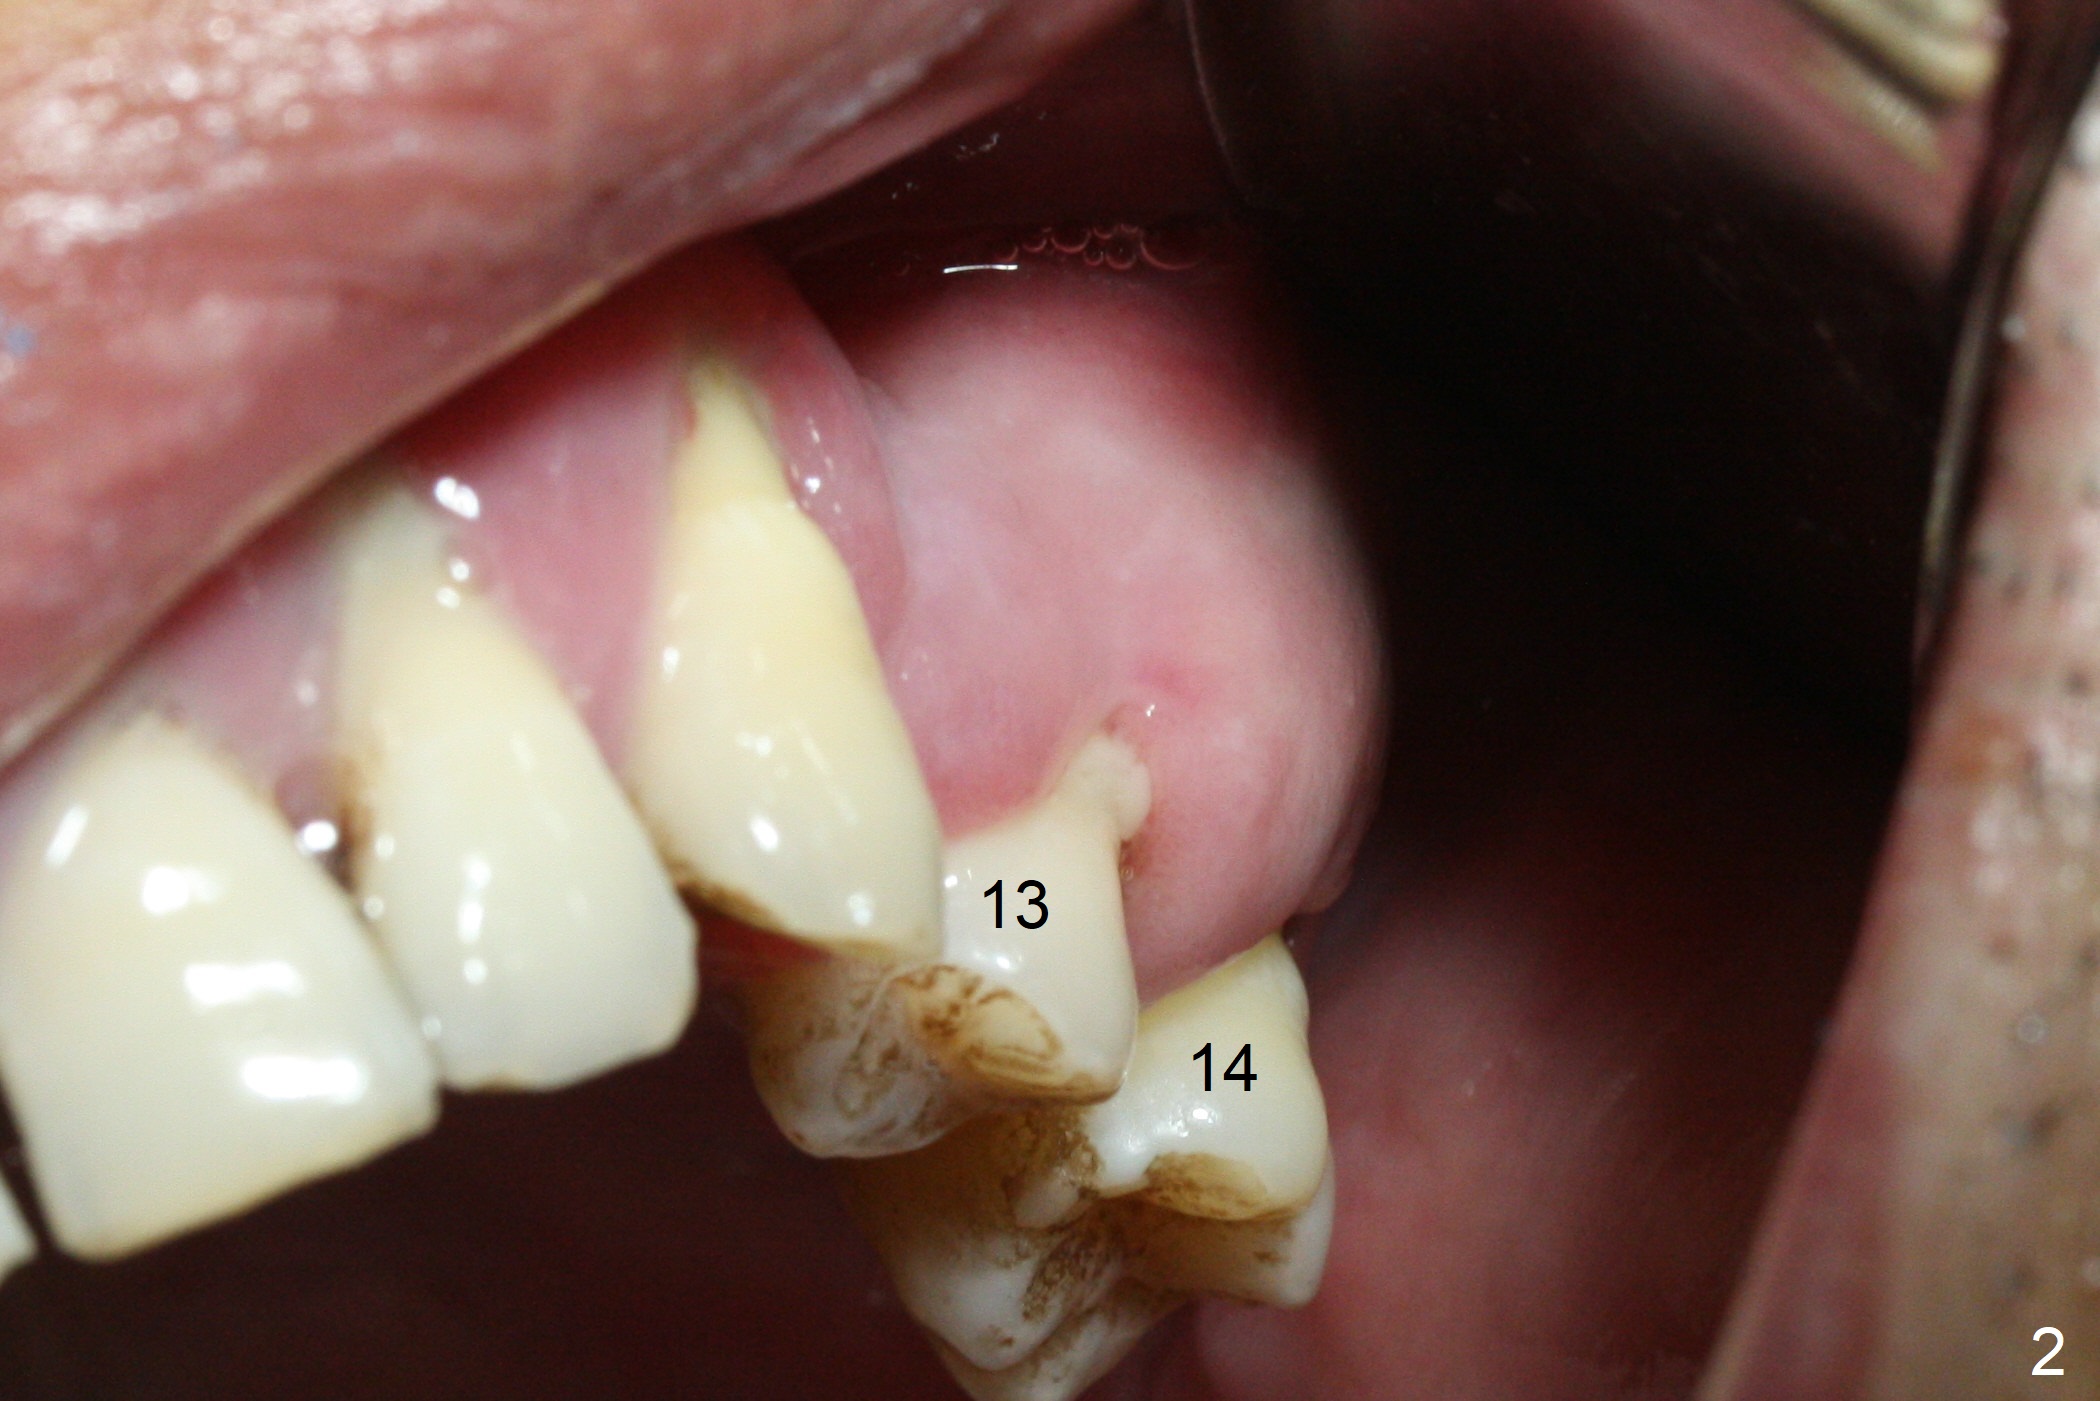

The 36-year-old man (ex-smoker, quit for 4-5 years) insists upon #3 and 5 extraction first for implants, in spite of more severe infection at #7, 14,19,30 (Fig.1-4). The gingiva around #23-26 implants is healthy 3 weeks postop (Fig.5). The initial depths at #3 and 5 are 8.5 mm (bone-level) and 18 mmm (gingiva-level (13 mm (implant length) + 5 mm cuff), respectively. When a drill penetrates the sinus floor, confirm the depth. After use of 3.8 mm drill, 4.5 mm tap drill is inserted at #3 without stability, while a 4.5x13 mm implant is placed at #5 with primary stability (Fig.6,7). Then a 5x11.5 mm is placed at #3 subcrestal proximally after sinus lift with Vanilla graft (without sinus membrane perforation; Fig.8). The implant at #5 is seated ~1 mm deeper (subcrestal mesially (^^); supracrestal distally (^)); allograft is placed around the implants prior to insertion of 6.5x7(5) and 5.5x4(5) mm abutments; last more allograft is added (Fig.9 *, 10). The implants seem to have been osteointegrated 4.5 months postop (Fig.11,12). The gingiva is healthy around the implants without bone loss 3 months post cementation (Fig.13,14).